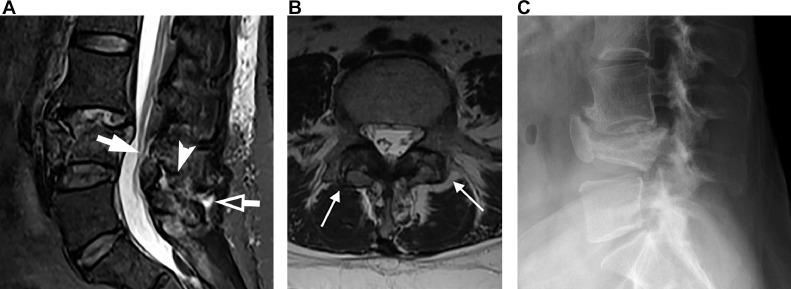

There were 67 separate injuries in 62 patients. Kyphosis measuring ≥ 10° developed despite an intact PLC in 6/14 nonoperative cases, and 3/7 surgically treated cases; when PLC was partially injured, it developed in 6/10 cases (8 treated nonoperatively, 2 treated operatively. Thirty injuries had complete disruption of PLC by MRI, 24 treated with fusion. Kyphosis ≥ 10° developed in 3/6 treated nonoperatively, and 8/24 treated with fusion. Development of kyphosis was independent of degree of vertebral body comminution. It developed equally in patients with Grade 2 and Grade 3 Denis injuries. It developed in patients with intact PLC when multiple vertebrae were involved and/or there was compressive injury to anterior longitudinal ligament (ALL). There was high interobserver variability in assessment of severity of ligamentous injury on MRI.

Classification systems of thoracic and lumbar spine injury and integrity of the PLC failed to predict the risk of development of post-traumatic kyphotic deformity.